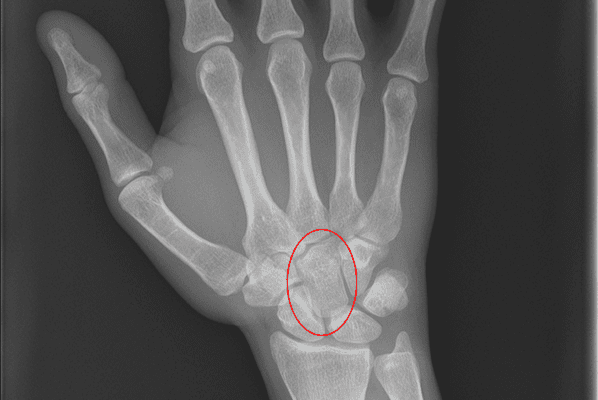

These are rare but devastating injuries. They can be associated with a carpal fracture. Fracture dislocations are twice as common as pure ligamentous dislocations. Isolated carpal dislocations are rare.

The most common Carpal dislocations are the lunate, the lunate with a scaphoid fracture, and perilunate dislocation.Carpal dislocations can lead to chronic pain and wrist instability. They are difficult to diagnose and are often missed.